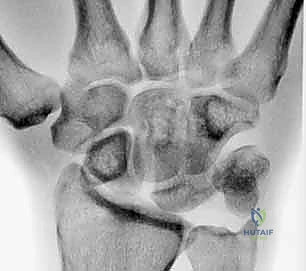

- Plain Radiographs: Often normal in dynamic LT instability. Clenched-fist anteroposterior, radial, and ulnar deviation views are essential. Look for disruption of Gilula arcs I and II, proximal translation of the triquetrum, or LT overlap, though a static LT gap is less common than in scapholunate injuries.

- Volar Intercalated Segment Instability (VISI): This is a more severe form of carpal collapse. While LT dissociation is a prerequisite, VISI requires additional compromise of secondary restraints, most notably the dorsal radiotriquetral ligament. Without the integrity of this extrinsic ligament, static carpal instability ensues, characterized by a volar-flexed lunate and an abnormal lunotriquetral angle. On a lateral radiograph, a normal lunotriquetral angle is approximately 14 degrees. In VISI, this angle can increase to -16 degrees or more, indicating volar flexion of the lunate.

FIG 1 • A. Intact dorsal ligaments and normal carpal alignment. Loss of integrity of these secondary restraint structures, the volar-flexed position of the lunate, and the resulting volar intercalated segment instability (VISI) carpal collapse. B. Normal anatomic alignment of the carpus as viewed from a lateral radiograph. The lunotriquetral angle is 14 degrees. C. VISI carpal collapse visible on lateral radiograph. The lunate is volar-flexed and the lunotriquetral angle is 16 degrees. D. Rupture of the lunotriquetral interosseous ligament and the dorsal secondary restraint.